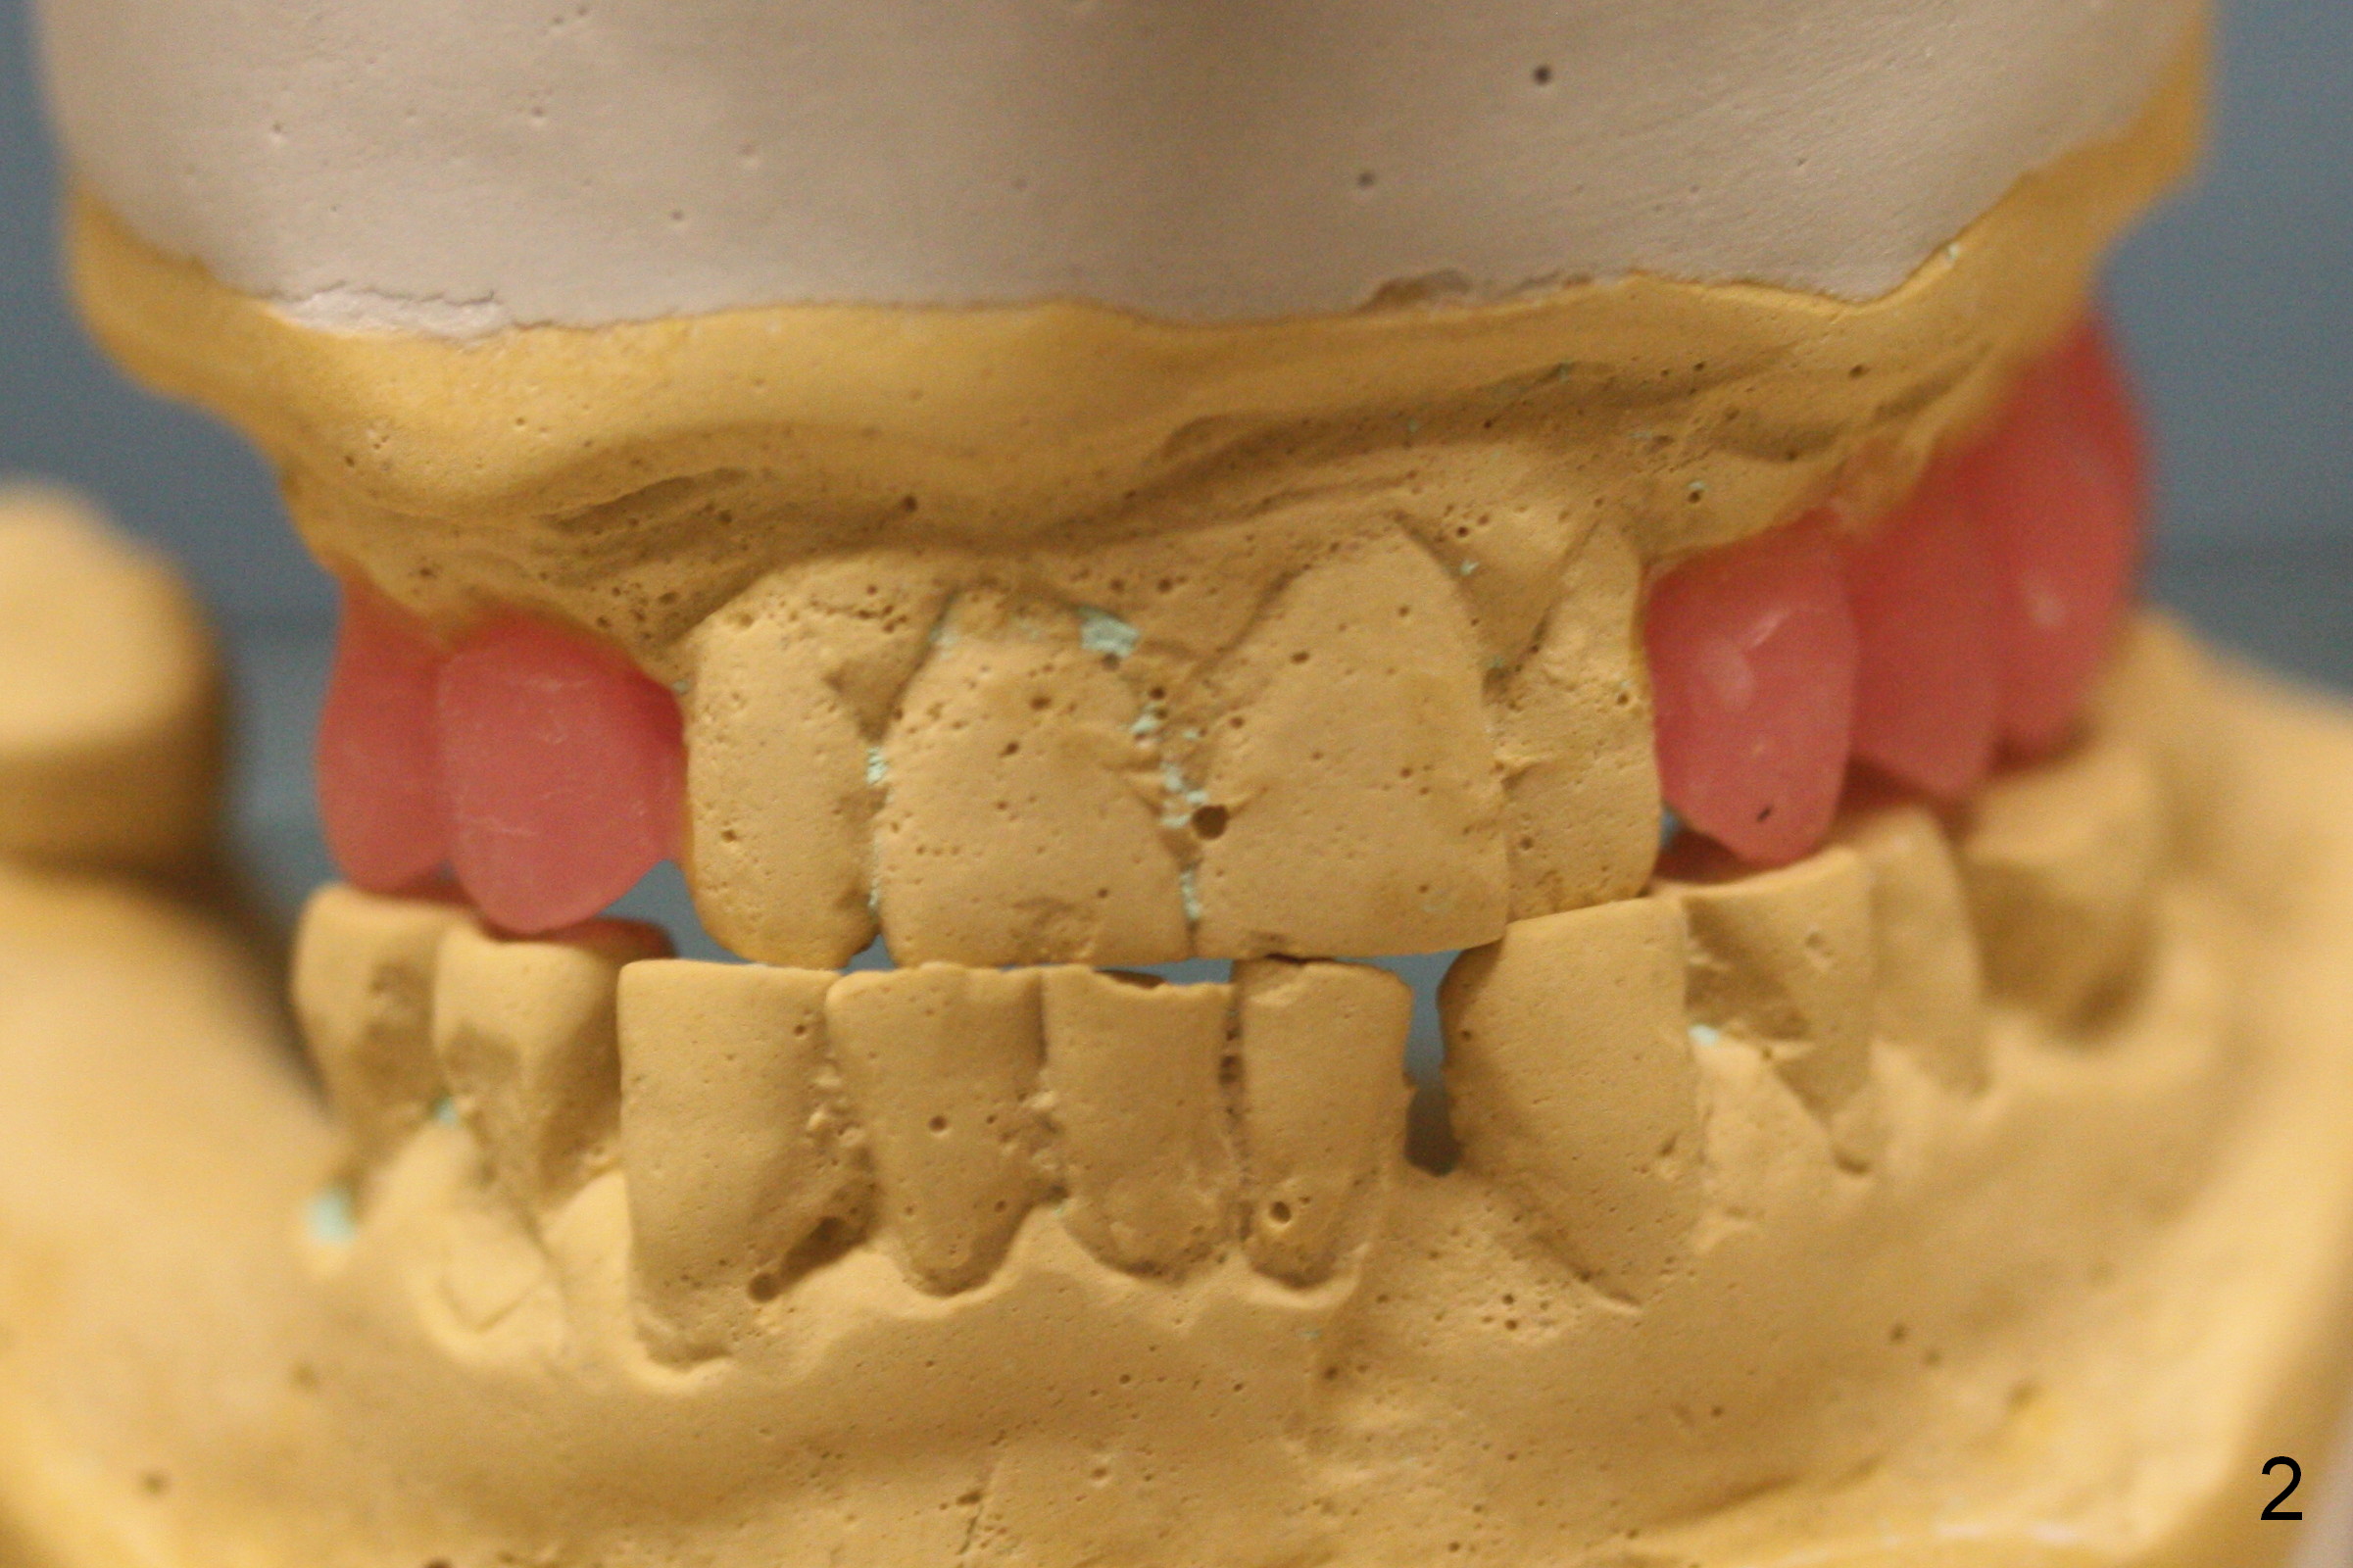

A 70-year-old man (CK) requests restoration of the upper arch with implants, because he is not used to a partial denture. Due to cross bite (Fig.1-3), one less implant can be placed in each of the posterior region (Fig.1, 3).

To avoid or reduce the chance of using an angled abutment at #6, the apical end of the implant should be placed as close to the buccal plate as possible (Fig.8 red arrow). Compare the angles at the implant crown (Fig.7,8). Initial osteotomy depth is 17 mm; insert parallel pins and take PA for checking trajectory (Fig.4). When fabricating provisional crowns, make sure that they are palatal to the lower counterparts (cross bite), both right and left.